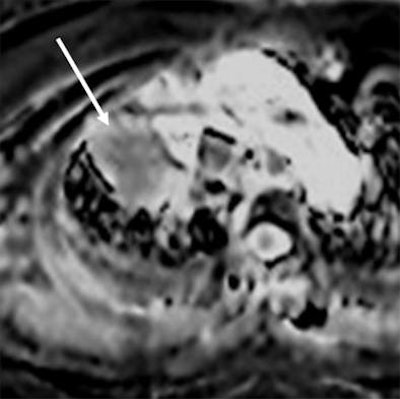

| MR images of a 75-year-old woman with lung cancer who achieved a partial response after two rounds of chemotherapy. ADC maps obtained before (above) and after (below) one course of treatment indicate that the ADC value of the lesion (arrow) increased from 0.99 to 1.48 x 10-3 mm2/sec after therapy. Images courtesy of Radiology. |